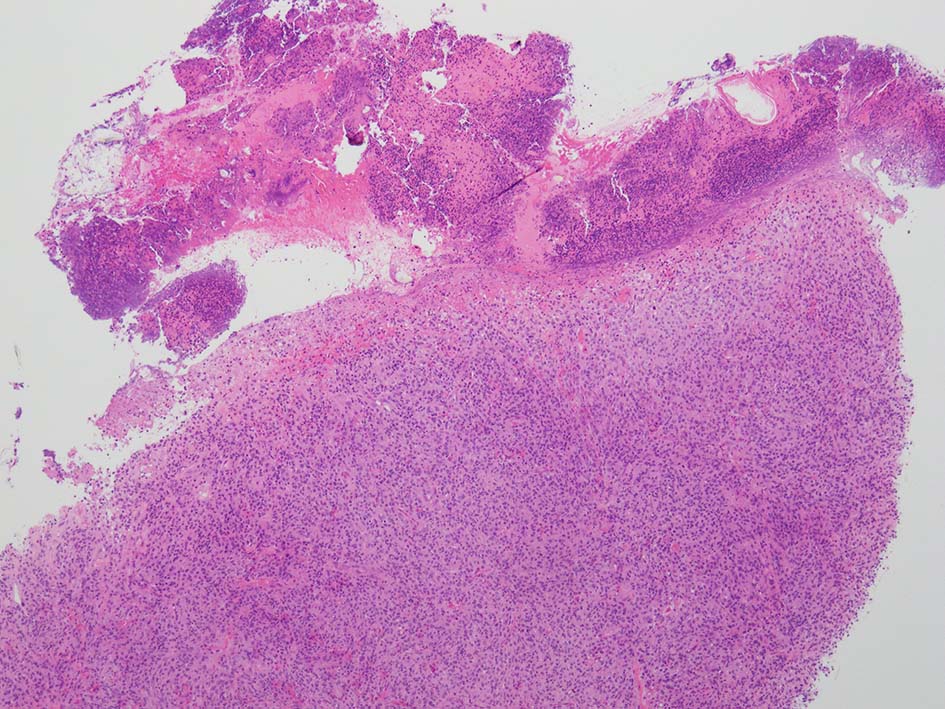

loupe像:表面に痂皮形成. 均等な組織像で,壊死や出血はみられない. 低倍ではspindle cellの密な増殖があるように見える. 拡大所見では, 類円形, 卵円形, ねじれた桿状の核, くびれ,勾玉様の核など不整形な核をもつ細胞が増殖している. クロマチンは繊細な傾向で, 核小体を1個もつ核が認められる. 高倍率10視野で 1-2個の核分裂像が数えられた.

樹状細胞性腫瘍, 組織球性腫瘍, histiocytic sarcoma(あまり異型がめだたない)などを考えて鑑別, 免疫染色をおこなった.